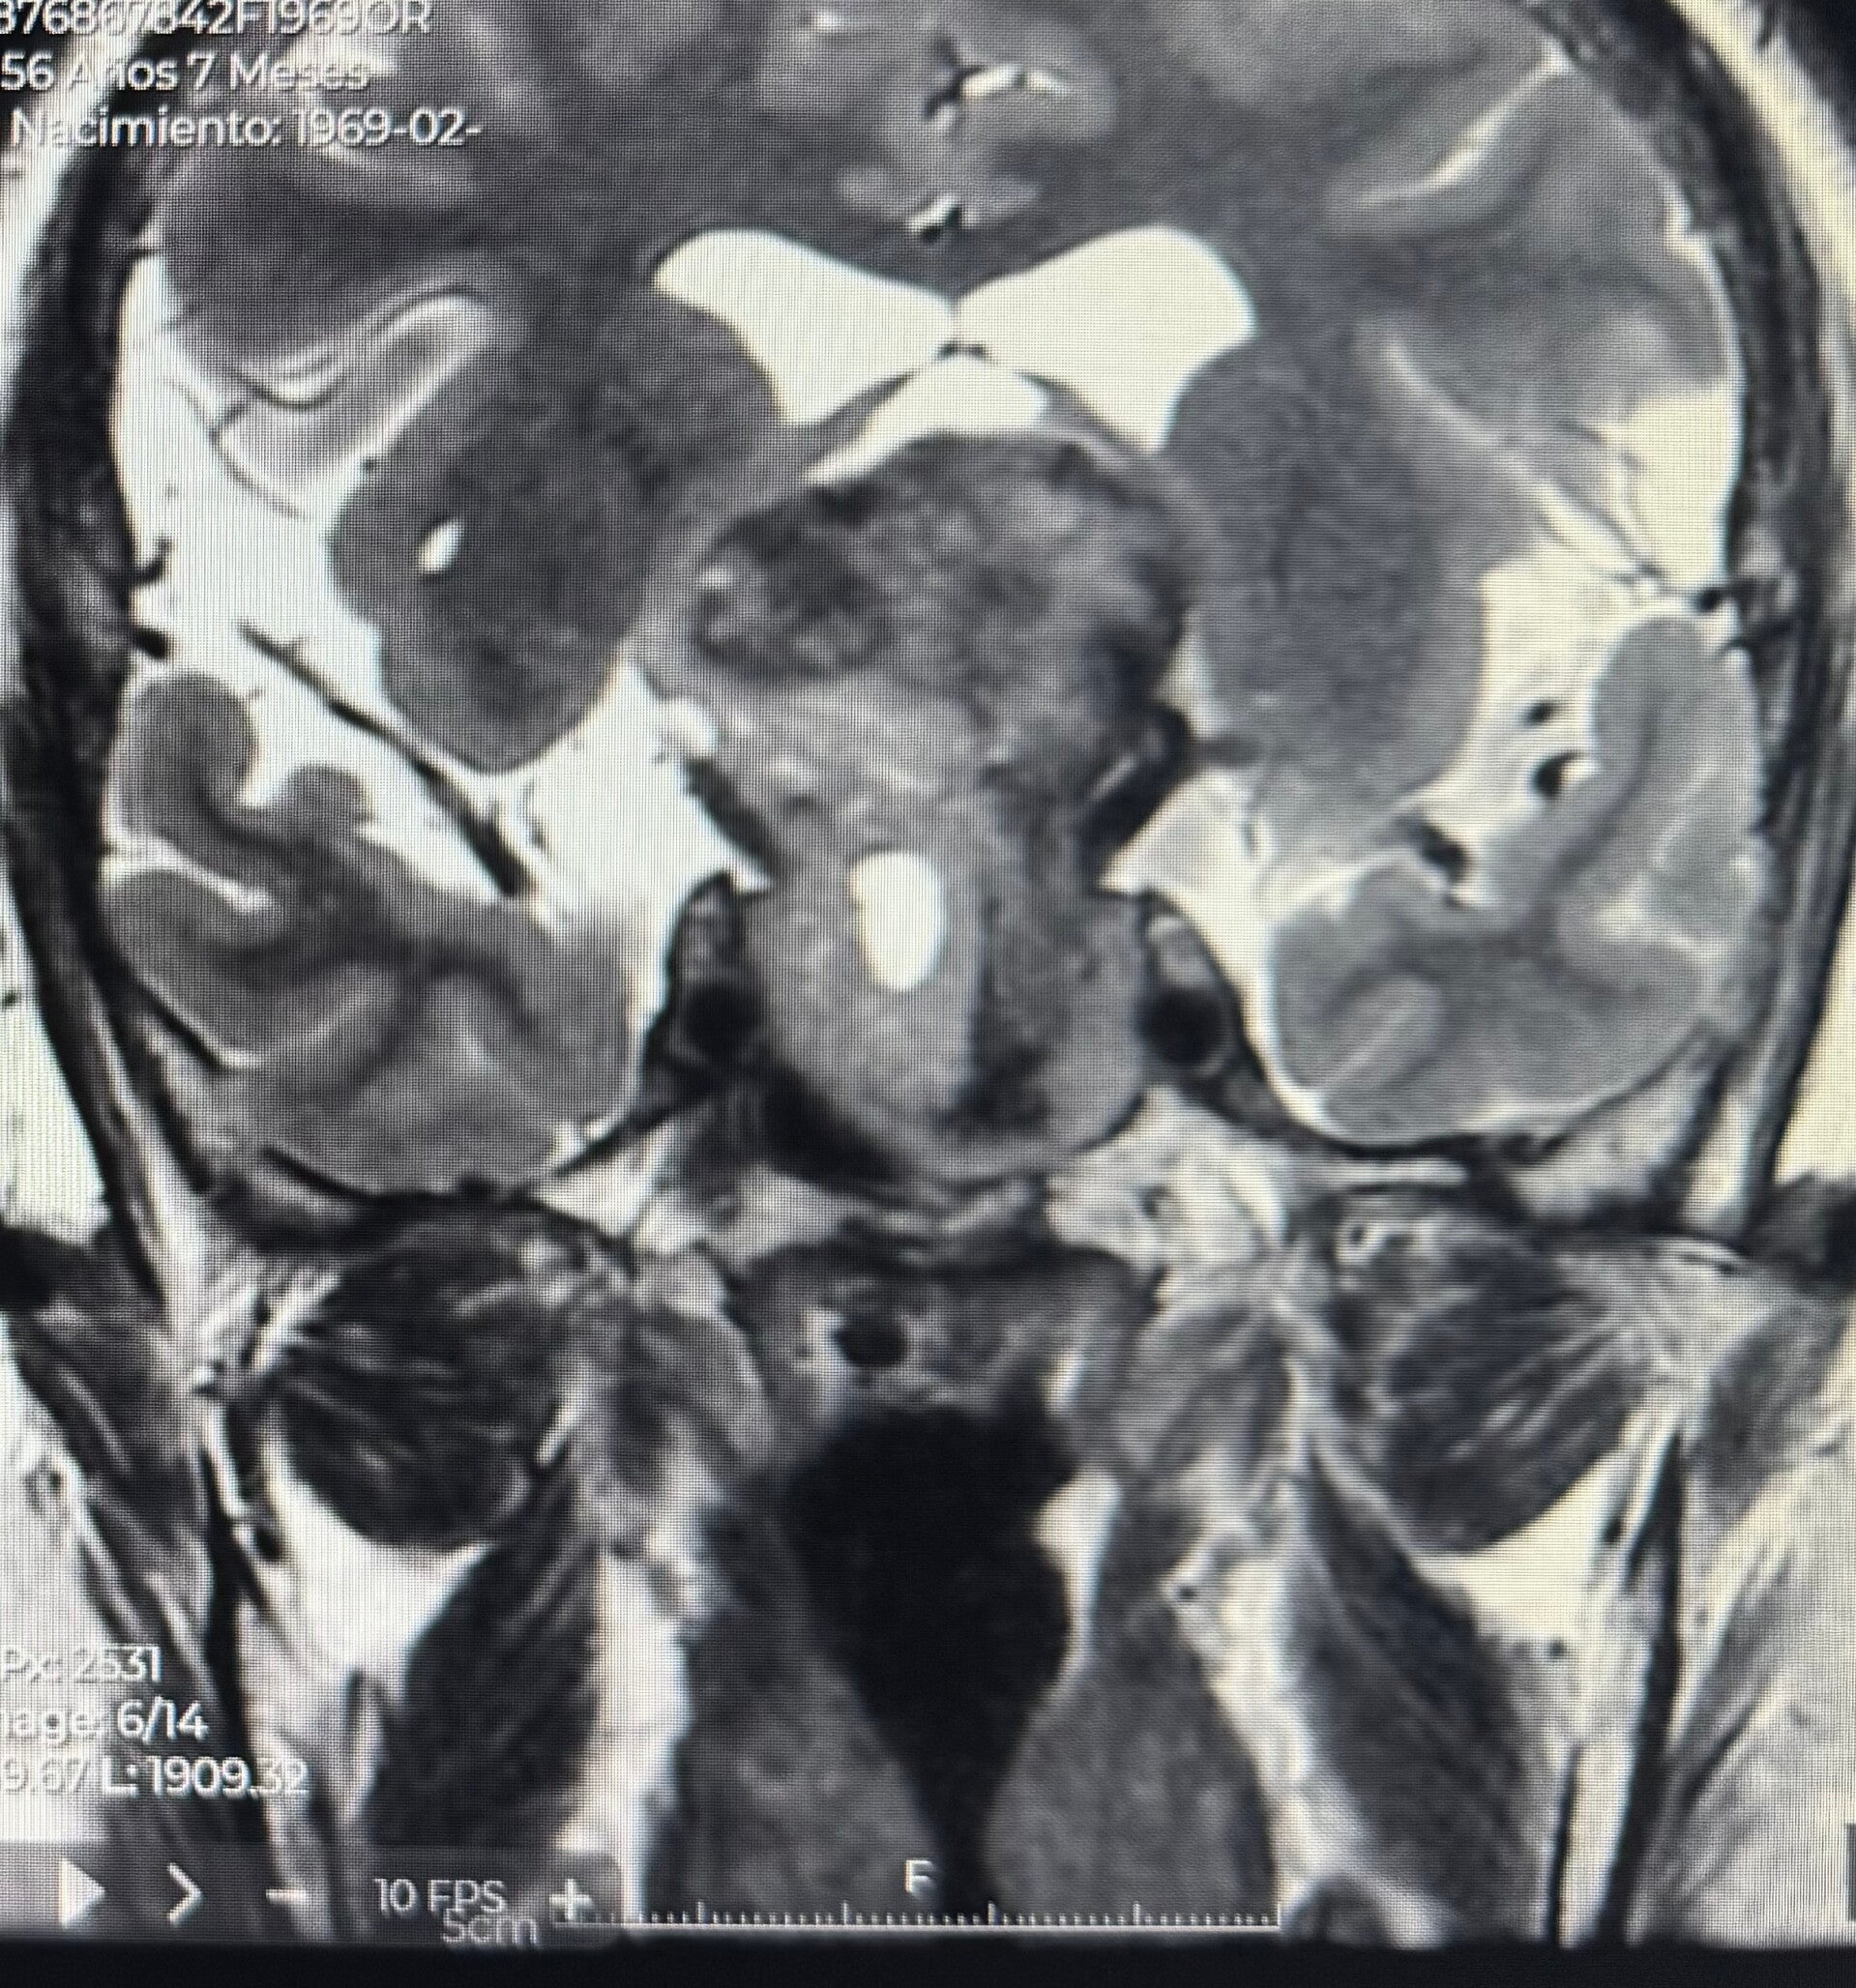

- Tumores cerebrales (Adenomas de Hipofisis, meningiomas, gliomas, entre otros).